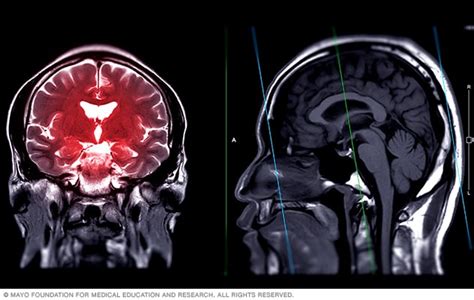

Un estudio reciente publicado en The Lancet Psychiatry aporta evidencia adicional sobre la base neurobiológica de este trastorno. La investigación, que abarcó a 3.200 personas de entre 4 y 63 años, es la más extensa hasta la fecha en medir el volumen cerebral de individuos diagnosticados con TDAH. El estudio comparó las diferencias estructurales cerebrales entre 1.713 personas con TDAH y 1.529 personas sin este diagnóstico. Se realizaron resonancias magnéticas a los 3.242 participantes para evaluar el volumen total de su cerebro y el tamaño de siete regiones específicas que investigaciones previas sugerían estaban vinculadas al TDAH: el pallidum, el tálamo, el núcleo caudado, el putamen, el nucleus accumbens, la amígdala y el hipocampo.

El TDAH se considera un trastorno psiquiátrico debido a que involucra el funcionamiento mental y causa deterioro significativo. Investigaciones con imágenes cerebrales y estudios neuropsicológicos demuestran diferencias en el cerebro de personas con TDAH, especialmente en la corteza prefrontal, responsable de la motivación y funciones ejecutivas.

Un estudio de 2016 en la Universidad de Radboud (Países Bajos) con 3.242 personas (1.713 con TDAH) encontró que el volumen cerebral era significativamente menor en los diagnosticados con TDAH, con disminuciones en siete áreas específicas.